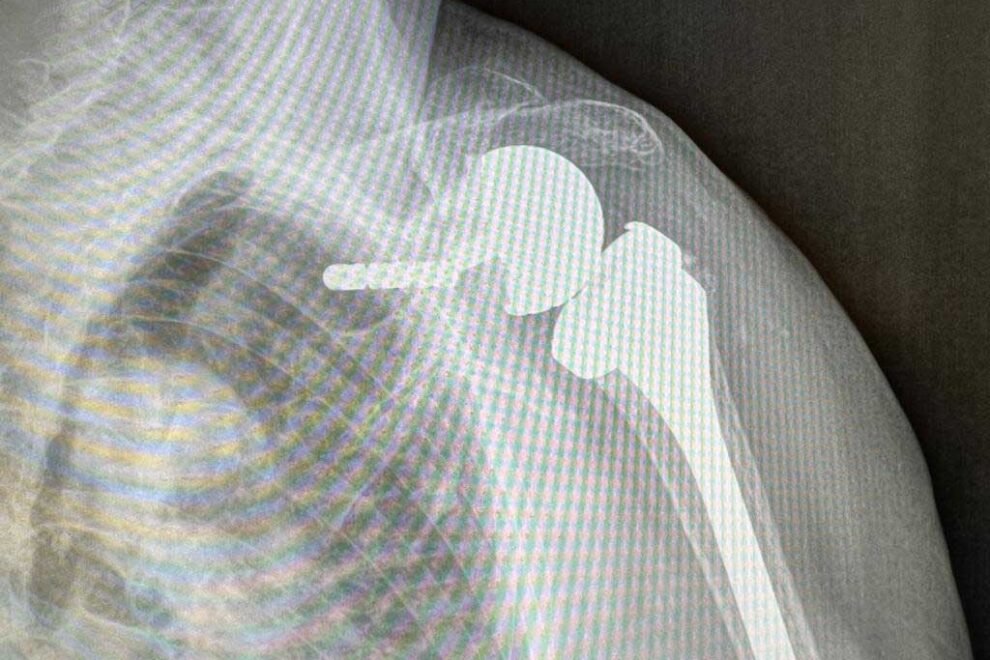

Cuffia dei rotatori: info intervento

Cuffia dei rotatori: info intervento. Per La diagnosi sono necessarie radiografie della spalla in anteroposteriore e proiezione tipo Bernageau e RMN Indicazione all’intervento Innanzitutto è sconsigliato operare quando la spalla è bloccata e cioè è in capsulite perché si potrebbero creare aderenze post-operatorie. Se la lesione è troppo vecchia o troppo grande od accompagnata da…